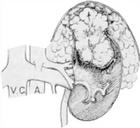

(3)腎動脈造影:腎動脈造影可發現泌尿系統造影未變形的腫瘤,腎癌表現有新生血管,動靜脈瘺,造影劑池樣聚集(Pooling)包膜血管增多。血管造影變異大,有時腎癌可不顯影,如腫瘤壞死,囊性變,動脈栓塞等。腎動脈造影必要時可向腎動脈內注入腎上腺素正常血管收縮而腫瘤血管無反應。

在比較大的腎癌。選擇性腎動脈造影時亦可隨之進行腎動脈栓塞術,可減少手術中出血腎癌不能手術切除而有嚴重出血者可行腎動脈栓塞術作為姑息性治療。